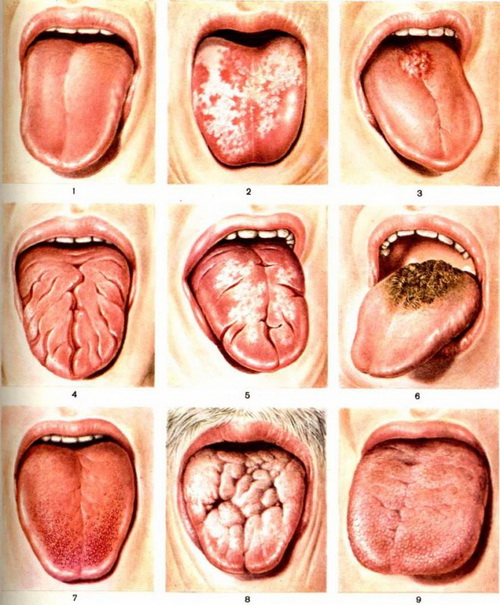

Глоссит

Глоссит – большая группа патологий, вызывающих нарушение структуры и изменение цвета языка. В группе риска — лица, отказывающиеся от регулярных гигиенических процедур. Инфекция проникает в толщу тканей языка при наличии травм, воспаления в ротовой полости или системе ЖКТ.

Предотвратить возникновение глоссита можно посредством ежедневного использования флоссов, гигиенических ополаскивателей, качественных зубных паст.

Глоссит

Глоссит – это воспаление слизистых оболочек языка.

При этом заболевании могут воспаляться:

- вкусовые сосочки, которые находятся на поверхности языка,

- слизистые оболочки подъязычной области.

Симптомы глоссита

Боль. Характерными являются болевые ощущения при приеме пищи, питье, а также разговоре. Иногда беспокоит жжение, саднение или даже онемение в области языка. Если инфекция проникла в область вкусовых сосочков языка, возникает нарушение вкусовых ощущений.

Отек. Этот симптом является нередким проявлением воспаления. При отеке язык увеличивается в размерах. При сильно выраженном воспалении из-за отека может нарушаться речь.

Изменения слизистой оболочки. Глоссит может проявляться покраснением слизистых оболочек языка, а также образованием язвочек, ранок, гнойничков и пузырьков, наполненных прозрачной жидкостью.